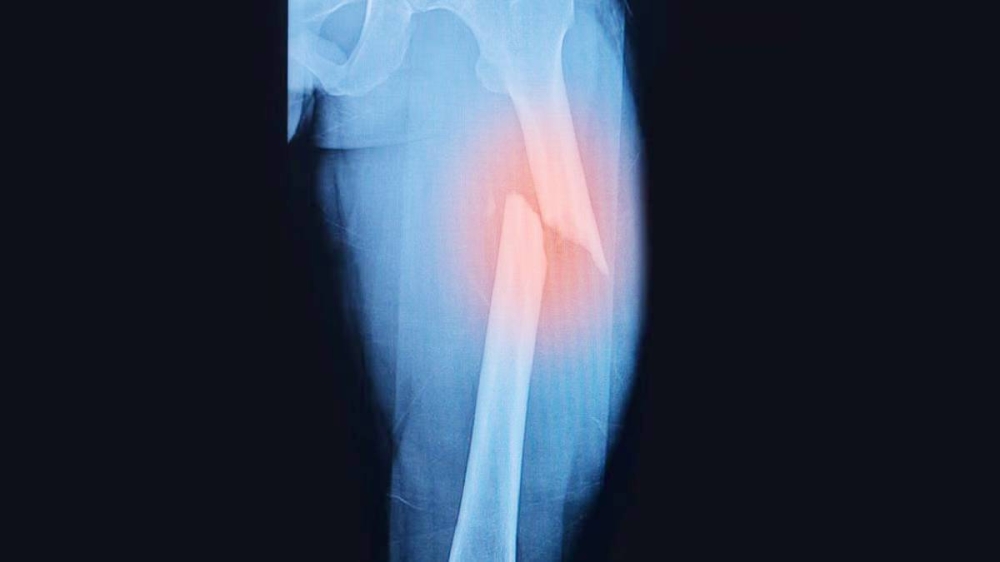

كشف علماء يابانيون، تقنية جديدة لشفاء العظام المكسورة، لا تسرِّع عملية التعافي فحسب، بل تعزز أيضاً قوة العظام بأكثر من ثلاثة أضعاف.

وباستخدام تقنية تشعيع البلازما، فإن النهج المبتكر يحمل وعداً بإحداث ثورة في علاج الكسور المعقدة؛ بحسب تقرير نشره موقع (Good News Network).

وأثبت الباحثون في جامعة أوساكا ميتروبوليتان، فعالية هذه الطريقة من خلال التجارب الناجحة على فئران المختبر.